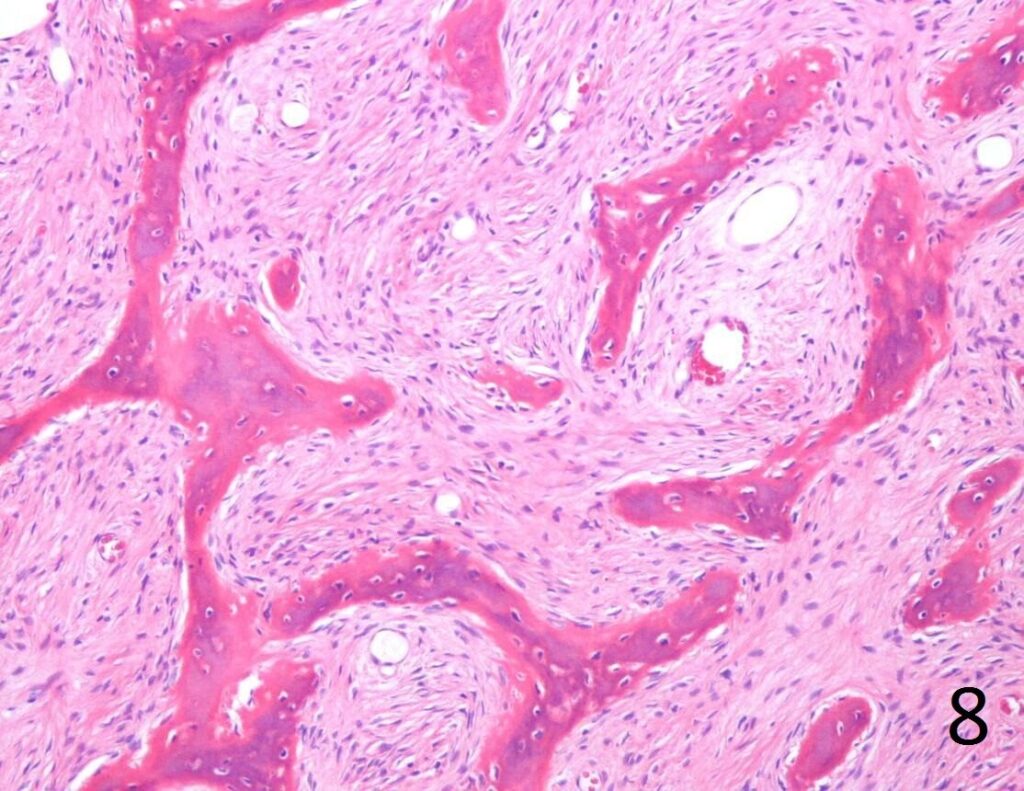

• Combination of bland hypocellular fibrous tissue with small fragments of woven bone without visible rimming by osteoblasts(Fig. 7-8) .

• The trabecule are common referred as Chinese characters, or resembling “Cs”and “Os”. Also may be called Alphabet Soup. This arrangement may mimic the appearance of Paget’s diseases

• Trabeculae are not lined with oteoblasts.

Fig. 8. Microscopic: Low power photograph of fibrous dysplasia shows a combination of bland fibrous tissue with small fragments of woven bone.